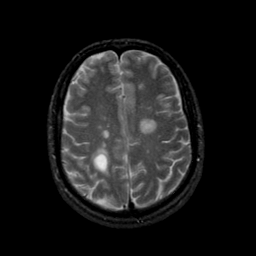

MR Study #9, April 14, 1991 -- Slice #36